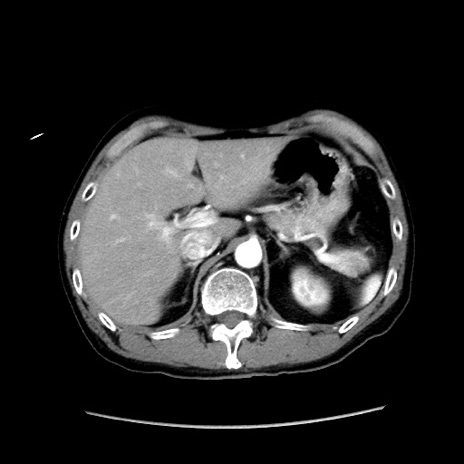

症例37(横断像)

【症例】40歳代 男性

【主訴】腹痛

【現病歴】4時間ほど前に電車に乗車中に臍部上より腹痛出現。徐々に増悪し起立困難となり、救急外来受診。生ものは数日食べていない。今朝お雑煮を食べた。

【身体所見】BT 36.8℃、BP 117/84mmHg、HR 91/min、SpO2 97%、苦悶様、腹部:臍上部広範囲圧痛あり、反跳痛±

【データ】WBC 8100、CRP 0.03